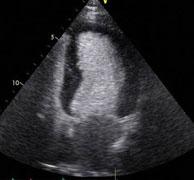

August 25, 2010 – Evidence suggests the use of contrast agents for echocardiography is safe and not associated with a greater incidence of myocardial infarction or mortality, according to a new study published in the American Journal of Cardiology (vol. 106, issue 5, pages 742-747, Sept. 1, 2010.)

In October 2007, the U.S. Food and Drug Administration (FDA) issued a black box warning for contrast agents used in patients undergoing echocardiography and restricted their use in patients with acute coronary syndrome, a decompensated heart and respiratory failure.

Eight studies were included in the meta-analysis. A random-effect model was used and between-studies heterogeneity was estimated with I2. Eight studies reported death as an outcome and only four reported myocardial infarctions. The incidence of death in the contrast group was 0.34 percent (726 of 211,162 patients) compared to 0.9 percent (45,970 of 5.08 million patients) in the noncontrast group. The pooled odds ratio was 0.57 (95 percent confidence interval 0.32 to 1.01, p = 0.05). The reported incidence of myocardial infarction in the contrast group was 0.15 percent (86 of 57,264 patients) compared to 0.2 percent (92 of 44,503 patients) in the noncontrast group. The pooled odds ratio was 0.85 (95 percent confidence interval 0.35 to 2.05, p = 0.72). Significant heterogeneity was seen among the studies.